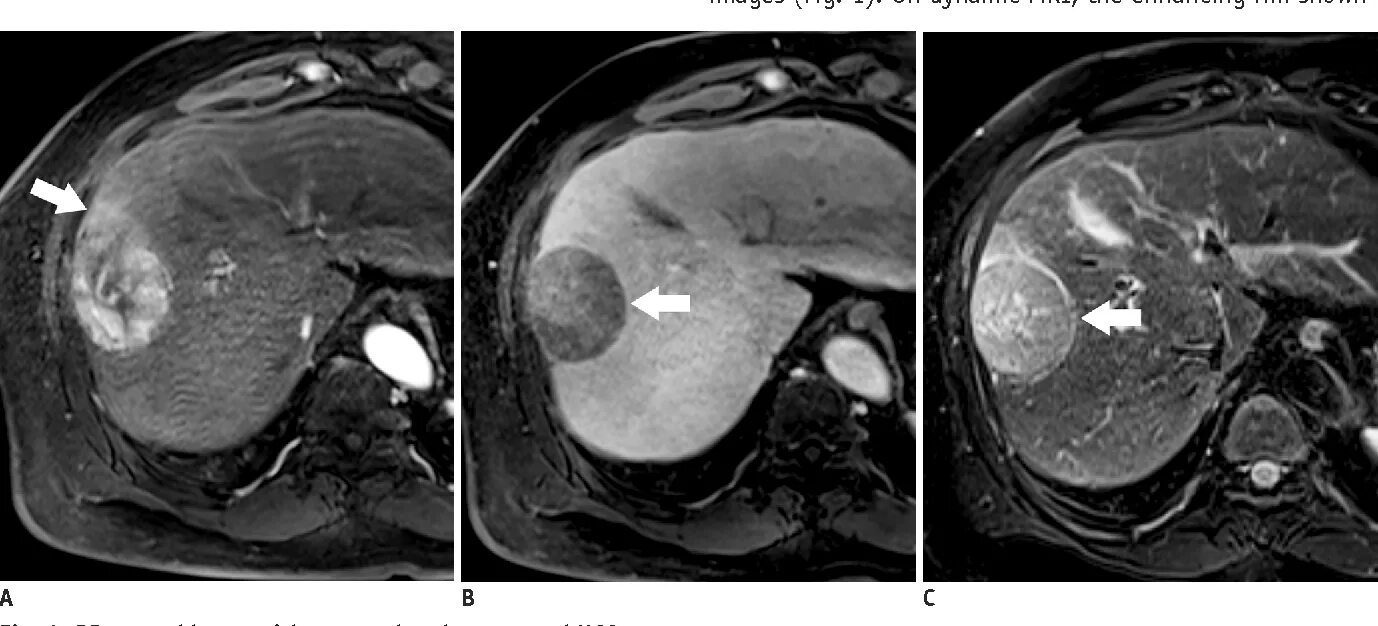

Очаговое образование молочной железы фиброаденома. Фиброзно-жировая инволюция молочных желез что это такое. Объемное образование в молочной железе. Злокачественные образования молочной железы. Фиброламеллярная карцинома печени мрт. Фиброламеллярная карцинома печени кт. Доброкачественная опухоль печени мрт. Гепатоцеллюлярная карцинома мрт.

Фиброламеллярная карцинома печени мрт. Фиброламеллярная карцинома печени кт. Доброкачественная опухоль печени мрт. Гепатоцеллюлярная карцинома мрт. Онкомаркеры локализация опухоли. Онкомаркеры презентация. Онкомаркеры в онкологии. Анализ на онкомаркер.

Классификация заболеваний щитовидной железы. Классификация хирургических заболеваний щитовидной железы. Заболевания щитовидной железы классификация этиология. 1. Классификация заболеваний щитовидной железы?. Опухоль печени доброкачественная кт. Первичные злокачественные опухоли печени. Злокачественные новообразования печени кт. Первичные и Метастатические опухоли печени.

Опухоль печени доброкачественная кт. Первичные злокачественные опухоли печени. Злокачественные новообразования печени кт. Первичные и Метастатические опухоли печени. Маммография. Маммограмма молочных желез. Маммография после 40 лет проводится.

Лимфангиома брыжейки кт. Лимфома брыжейки тонкой кишки кт. Злокачественные новообразования печени кт. Объемное образование печени на кт.

Злокачественные новообразования печени кт. Объемное образование печени на кт. Клиника опухолей височной доли. Опухоль височной доли головного мозга диагностика. Симптомы поражения лобной доли головного мозга опухоль. Очаговые симптомы опухоли височной доли.

ПЭТ кт томограмма. Кт, ПЭТ И ПЭТ/кт. ПЭТ кт с контрастом. Скопление контраста ПЭТ кт. Метастатическое поражение печени. Метастатические опухоли печени. Злокачественные образования печени.

Метастатическое поражение печени. Метастатические опухоли печени. Злокачественные образования печени. Молочная железа маммография. Мастопатия на маммографии. Опухоль молочной железы маммограмма. Рик молочной железы маммографич.